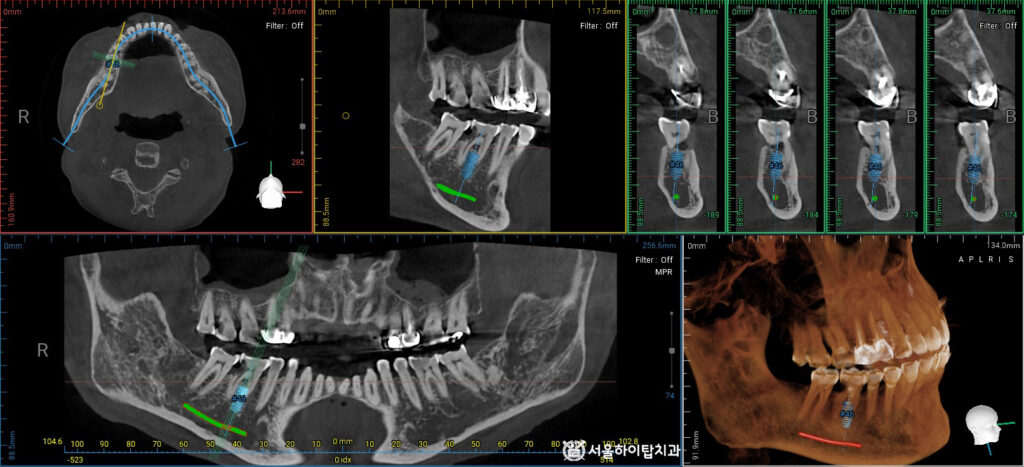

임플란트 가상 식립 시뮬레이션

이에 따라 발치를 결정하고,

가상 식립 시뮬레이션을 통해 임플란트가 심겨질 위치와 각도, 깊이를 사전에 계획합니다.

단순히 치아를 제거하는 것이 아니라,

주변 치조골의 형태와 골량을 분석하여

가장 안정적인 위치에 식립할 수 있도록 준비합니다.

만수동 치과 에서는 이러한 사전 계획을 통해 수술의 정확도를 높이고,

보철물까지 고려한 기능적 결과를 예측할 수 있다고 설명해 드립니다.